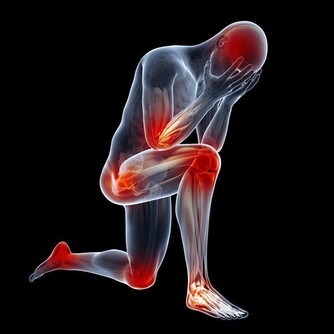

3、或是心功能減退。手腳冰冷和心臟功能有很大的關係,因為血液是由心臟發出,攜帶氧氣到全身各部位,糖經過氧化後,才能產生熱能,手腳才會溫暖。一旦心功能減退,就會影響血液運行輸送,造成手腳冰冷的情形。比如心臟衰弱會導致身體末梢部位血液供應大幅減少,使末梢溫度降低。

4、血管疾病。有些血管疾病比如常見於青年女性的雷諾病、大動脈炎,多發於中年男性的血栓閉塞性脈管炎,會影響人體末梢部位的供血。